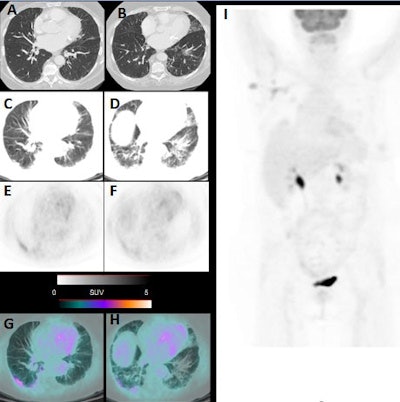

Italian researchers reported that several patients who entered their facility asymptomatic for the novel coronavirus later showed signs of pneumonia on CT and FDG avidity on PET, which made them suspicious for COVID-19. By acting upon the incidental detection of COVID-19 pneumonia in its early stages, subsequent preemptive steps could help prevent the spread of the virus.

Between 16 March and 24 March, the nuclear medicine department in Brescia performed 65 FDG PET/CT scans (Discovery ST or 690 scanner, GE Healthcare) for routine oncological indications. All the patients were asymptomatic for the COVID-19 virus, but they were carefully screened before their admittance to the nuclear medicine unit, given the outbreak of SARS-CoV-2 infections in northern Italy. No reason was found to suspect COVID-19 at that time.

Following completion of the scans, six patients (9%) showed signs of pneumonia on CT and FDG avidity in all areas of pneumonia, which made these patients suspicious for COVID-19. The six patients included four women, between 55 and 65 years old, and two men, ages 65 and 77, respectively. When physicians followed up with reverse transcription polymerase chain reaction (RT-PCR) tests, five patients (83%) were confirmed to have COVID-19.